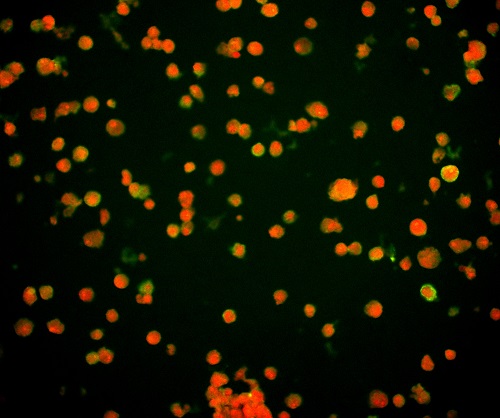

(1)通過觀測(cè)對(duì)病毒進(jìn)行特異性標(biāo)記產(chǎn)生的熒光信號(hào),從而實(shí)現(xiàn)對(duì)病毒位置數(shù)量的判斷。病毒主要由核酸和蛋白質(zhì)組成,常見的一種方法是利用熒光標(biāo)記的特異核酸探針與病毒含有的靶DNA分子或RNA分子進(jìn)行雜交,可通過在熒光顯微鏡下觀察熒光信號(hào),來確定與特異探針雜交后被染色的病毒的分布和數(shù)量,這種方式也稱為原位熒光雜交技術(shù)(FISH)。

FISH做的病毒檢測(cè),紅色為病毒外殼蛋白

(引自公開論文https://doi.org/10.1073/pnas.1820132117)